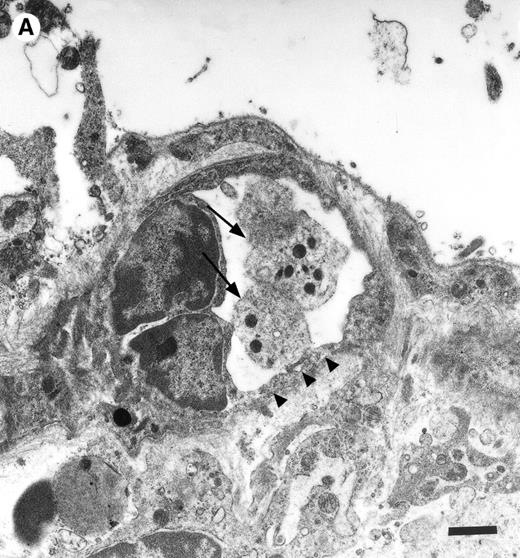

Platelets in postischemic microvasculature visualized by electron microscopy. There are no defects in the endothelial cell layer (arrowheads) Platelets (arrows) attach directly to endothelial cells (arrowheads). Bars represent 1 μm. Original magnifications: 7,000× (A) and 12,000× (B). NCL, endothelial cell nucleus.

In the physiologic state without I/R, circulating platelets rarely interacted with the microvascular endothelium (Figs1 and 2). Few platelets were observed rolling along the endothelial cell lining of arterioles and postcapillary venules (0 ± 0 and 3 ± 1 platelets/s/mm, respectively). At the same time, only 26 ± 14 and 28 ± 11 platelets were found firmly attached per mm2endothelial cell surface of arterioles and venules, respectively. In contrast, 1.5 hours of ischemia dramatically enhanced platelet-endothelial cell interactions immediately after postischemic reperfusion (Figs 1 and 2). As reported earlier, postischemic platelet accumulation involved arterioles, as well as venules. More than 15 platelets/s/mm vessel diameter were seen rolling along the arteriolar and venular vessel wall, respectively. At the same time, the number of firmly adherent platelets had increased 20- and 12-fold in arterioles and venules, compared with sham-operated animals (Fig 1). Platelet aggregation was a prominent phenomenon. Electron microscopy demonstrated that single or aggregated platelets adhered directly to endothelial cells; obvious defects in the endothelial cell layer were not detected (Fig 3).

Endothelial denudation was not observed in the present study, as demonstrated by electron microscopy. Instead, the deposition of fibrinogen occurred directly on the endothelial cell surface, indicating that the attachment of fibrinogen to endothelial cells might be mediated by a fibrinogen receptor present on the endothelium. Recently, the functional role of ICAM-1 as a novel fibrinogen receptor has been emphasized. ICAM-1 has been shown to contain a fibrinogen recognition site that is distinct from previously recognized ICAM-1 ligand binding regions.34 Through its ICAM-1 recognition, fibrinogen enhances the adhesion of leukocytes to endothelial cells in vitro and in vivo,18,19 and supports transendothelial monocyte migration.35 In addition, fibrinogen–ICAM-1 bridging has recently been demonstrated to mediate platelet adhesion to HUVECs in vitro.21 In the present study, the lack of endothelial ICAM-1 expression attenuated fibrinogen deposition to the postischemic vessel wall. In addition, in the absence of ICAM-1 platelet adhesion was significantly reduced, indicating that through its fibrinogen recognition, ICAM-1 promotes platelet adhesion to the postischemic endothelium in vivo. This mechanism might be of particular importance in mediating platelet adhesion to atherosclerotic lesions, which are characterized by the large deposition of fibrin(ogen) and the increased expression of ICAM-1.36-38 The established role of both fibrinogen and soluble ICAM-1 as a major risk factor for myocardial infarction further highlights the potential pathophysiologic relevance of platelet adhesion to endothelial cells via fibrinogen bridging to ICAM-1.39-41